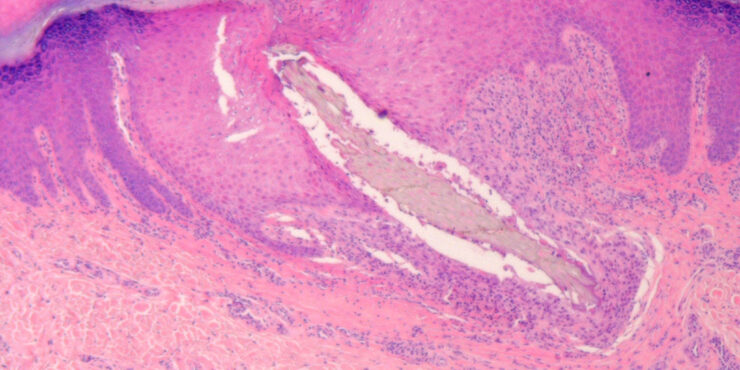

Spindle cell nevus = الوحمة مغزلية الخلايا